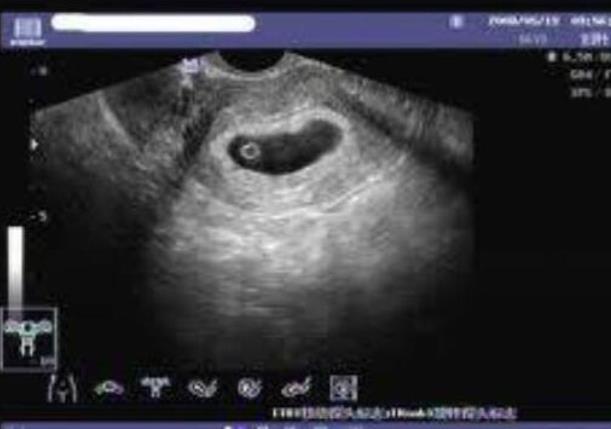

試管嬰兒等到受精卵放入子宮里面之后就需要保胎了,但也不是隨意的打黃體酮的,也需要看胎兒的發育情況來決定,如果一切正常就不需要打針。因為有的試管媽媽在懷孕的早期會有少量出血的癥狀,這個時候胚胎并不穩定,比如媽媽身體內的孕酮很低,那么就需要打黃體酮來保胎了。試管媽媽除了藥物保胎之外,同時還需要注意作息時間,前三個月一定要多休息,重體力活是肯定不能做的,精神也不要太緊張。

一般,醫生會在移植前,檢查你的雌二醇值、子宮厚度,如果不達標的話是不會手術滴!所以,你已然移植了,證明一切檢查值是正常的。另外,成功受孕的關鍵是:子宮厚度(8-12CM)、雌二醇值(會在移植后產生孕激素,維持合適的子宮厚度供胚胎著床)、孕酮值(越高越好,促進胚胎著床與發育)試管本來成功率就不及外界宣揚的那么高。一般要嘗試二次以上,一次的成功機率太小了。移植后,頭四天臥床休息,后面就要開始適度活動,但不能太勞累,如果出現腰酸、子宮墜痛要及時休息。其實,除了人力因素外,關鍵還是看胚胎自己,如果它能著床,且質量過關,就大功告成了。放輕松點!